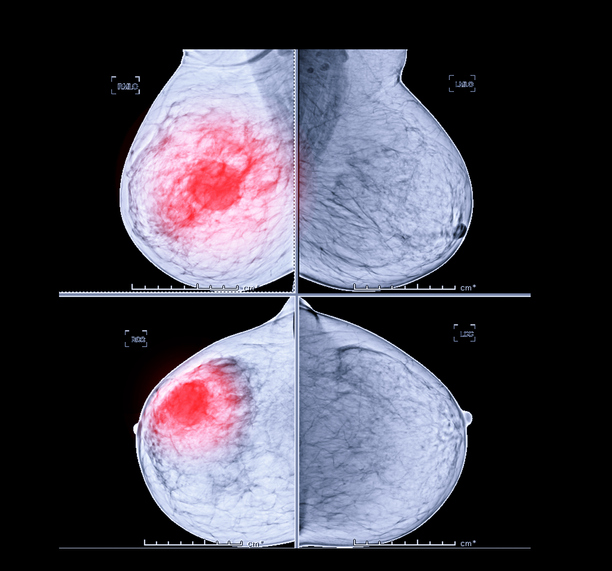

유방암 자가검진하기

유방암 자가 검진에는 육안 및 촉각 검진 방법이 있습니다. 전신 거울 앞에 서서 유방의 윤곽, 대칭, 움푹 들어간 곳이 있는지 확인합니다. 엄지와 약지를 제외한 가운데 세 손가락으로 유방의 덩어리나 피부 변화를 만져봅니다. 유두에서 비정상적인 분비물이 나오는지, 겨드랑이에서 덩어리가 만져지는지 확인할 수도 있습니다.

유방암 초기증상에 대해서 알아보았습니다. 나라에서 진행하는 건강검진을 통해서 40세부터 2년에 한 번 유방암 검진을 무료받을 수 있으므로 꼭 정기적으로 검진받으시고 건강 관리하시기 바라며, 알려드린 내용으로 건강 관리에 유의하시기 바랍니다.